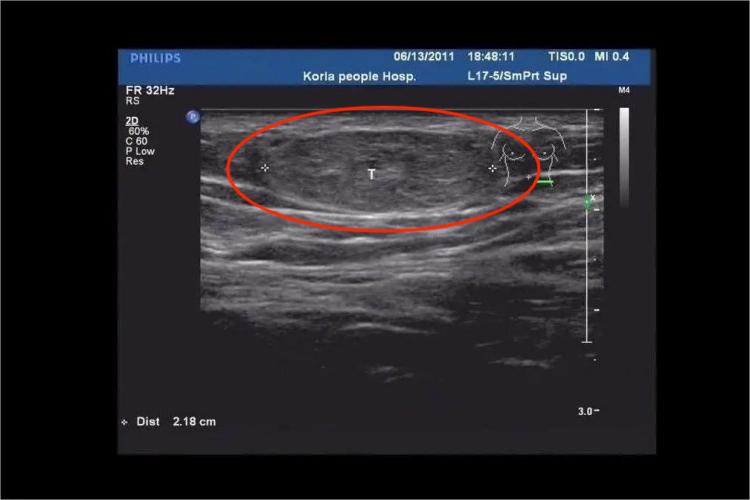

脂肪瘤超声常呈高回声,较为均匀一致,形状为圆形、椭圆形。

肌间脂肪瘤:发生于躯体肌肉间,超声表现为瘤体高回声,包膜呈清晰带状高回声,肌肉收缩时更明显,瘤体内部可见平行分布的纤细条状分隔。